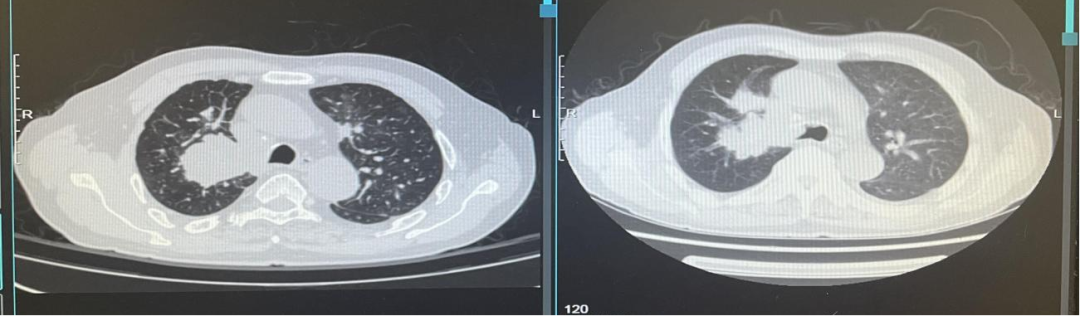

疾病进展:2021年8月,患者出现咳胸闷,咳嗽。胸部CT提示双肺转移瘤相仿,右侧支气管内多发软组织密度影。

图24、胸部增强CT显示支气管内新增转移病灶:左(2021-07-06)、右(2021-08-31)